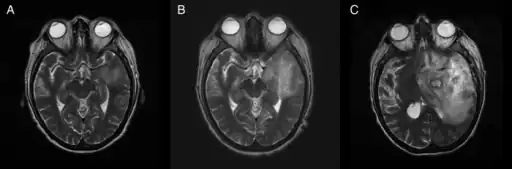

Image of granulomatous amoebic encephalitis caused by Acanthamoeba

A: T2-weighted MRI showing liquefied, necrotic brain tissue as a result of GAE caused by Balamuthia mandrillaris

B: T1-weighted MRI showing expansion and addition of necrotic areas 4 days later